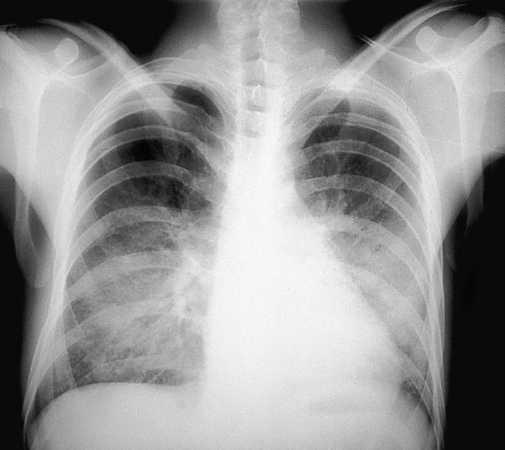

Se indicará profilaxis primaria frente a PCP en todo paciente con recuento de linfocitos CD4 menor de 200/µl, historia de candidiasis oral o episodio definitorio de sida asociado. Dicha recomendación deberá considerarse también en pacientes con recuentos de linfocitos CD4 superiores a 200/µl pero con porcentajes inferiores al 14% criterio definitorio de sida o cargas virales elevadas factor de riesgo independiente para el desarrollo de infecciones oportunistas7-9. Los pacientes que han presentado una PCP (figs. 1 y 2) deberán mantener una profilaxis secundaria para prevenir recidivas. En las tablas 1 y 2 se resumen las pautas recomendadas siendo el trimetoprim-sulfametoxazol (TMP-SMX) el fármaco de elección.

Fig. 1. Radiografía de tórax de un pacientes con sida con una neumonía por P. carinii que muestra el típico patrón intersticial bilateral.